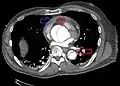

CT with contrast demonstrating aneurysmal dilation and a dissection of the ascending aorta (type A Stanford)

Chest CT with descending (type B Stanford) aortic dissection (red circle)

Type A dissection with pericardial effusion as a result.